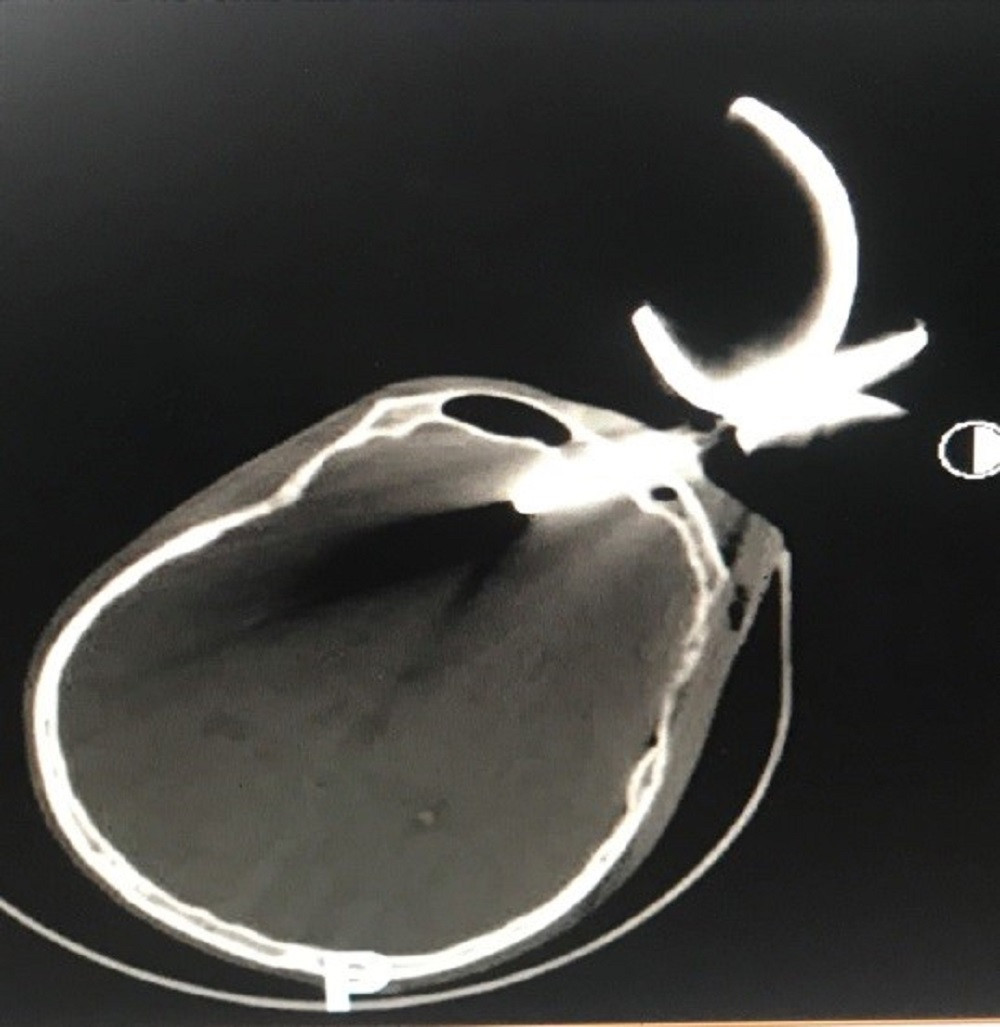

| Kết quả kiểm tra hình ảnh của bệnh nhân |

Ngay lập tức, các bác sĩ đã khẩn trương chụp CT-Scan sọ não cho bệnh nhân. Kết quả kiểm tra hình ảnh cho thấy, dị vật đã đâm xuyên xương sọ vào nhu mô não trán, độ sâu vết thương khoảng 4cm, vị trí ngay cực trán nên bệnh nhân có nguy cơ tử vong rất cao.